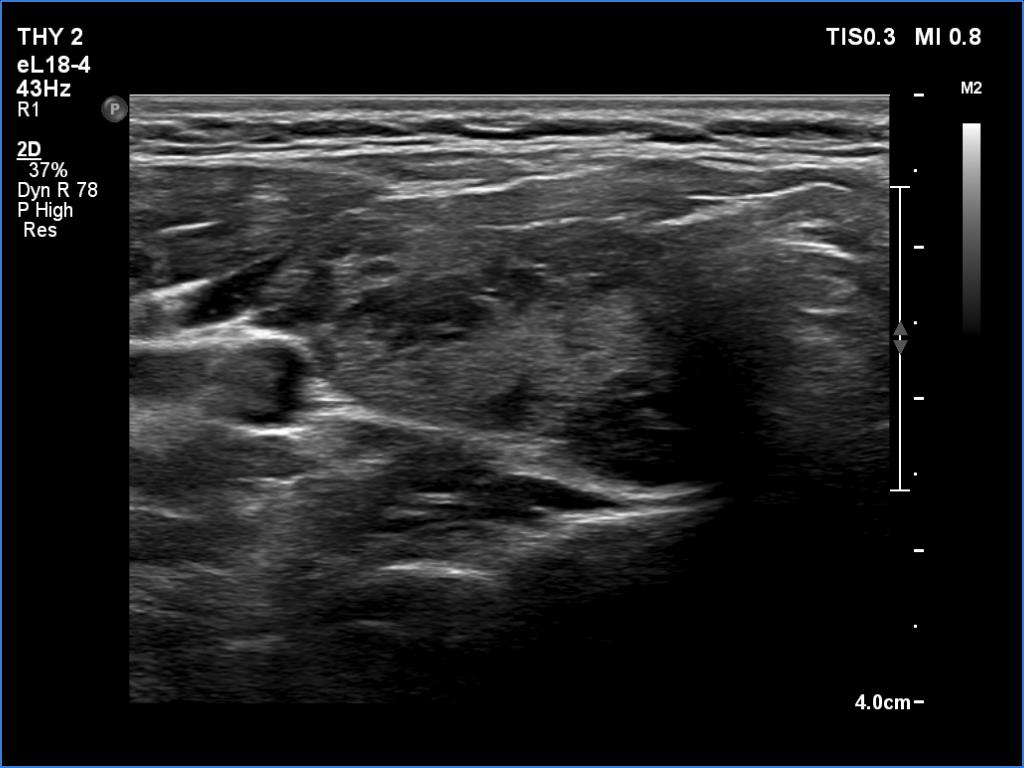

Ultrasonography. The thyroid was echonormal and had hypoechoic areas. The echogenicity index exceeded 50%. The pattern did not correspond to nodule. The vascularity was not specific.

Compared with the previous examinations, the ultrasound pattern remained unchanged.

Comment. This is the most common presentation of Hashimoto's thyroiditis, unfortunately not infrequently misinterpreted as a multinodular goiter. The multiplicity and the irregular borders of the discrete lesions are the main clues to avoid misinterpretation of these lesions as nodules.